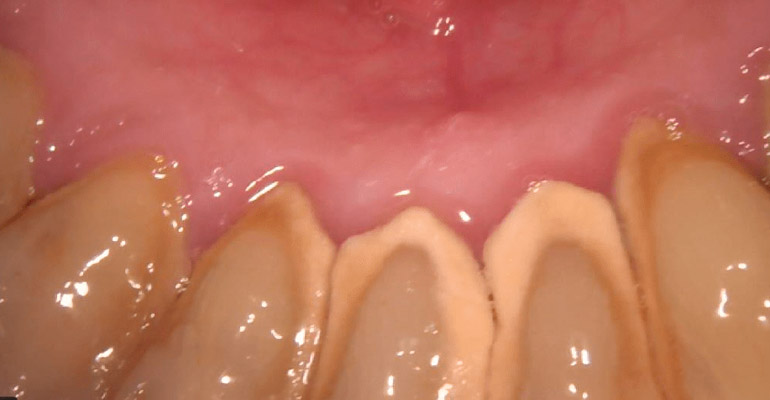

PERIODONCIA

CASOS CLÍNICOS

A continuación puede visualizar algunos clasos clínicos realizados en nuestra clínica, podrá informarse sobre el tratamiento realizado y visualizar las imágenes reales antes y después de nuestro tratamiento.

Todas las imágenes son de pacientes reales, algunas imágenes pueden herir su sensibilidad.

Pulse sobre las pestañas superiores para visualizar los diferentes casos clínicos.

Paciente periodontal con caries incipientes radiculares y desgaste oclusal por bruxismo.

Se realizo una rehabilitación con coronas para restablecer dimensión vertical y estética.